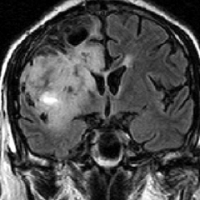

若い成人です,認知機能障害で発症しました。この画像を見るからに悪性神経膠腫,少なくともグレード3のグリオーマであることは明白です。しかし,グレード4膠芽腫あるいはグレード3退形成性星細胞腫にしては腫瘍周辺浮腫が軽すぎます。ですから,グレード3の退形成性乏突起膠腫 AO かも。認知機能の回復と温存を考量して,脳梁損傷と前交連損傷を避けて,右上前頭回と帯状回腫瘍を摘出しました。

左は術後のT1強調ガドリニウム増強像で,残存腫瘍がわかります。この腫瘍に対してICE (IFO/CDDP/VP-16) 化学療法を1コースしました。右側のMRIが1ヶ月後の画像です。このように1p/19q欠失のある退形成性乏突起膠腫は,化学療法感受性がとても高い悪性グリオーマです。ですから,手術で後遺症を残さないように,勢い込んで腫瘍を摘出しようとしないことが大切です。光顕診断はAOで,後々の解析で1p/19q codeletion でした。